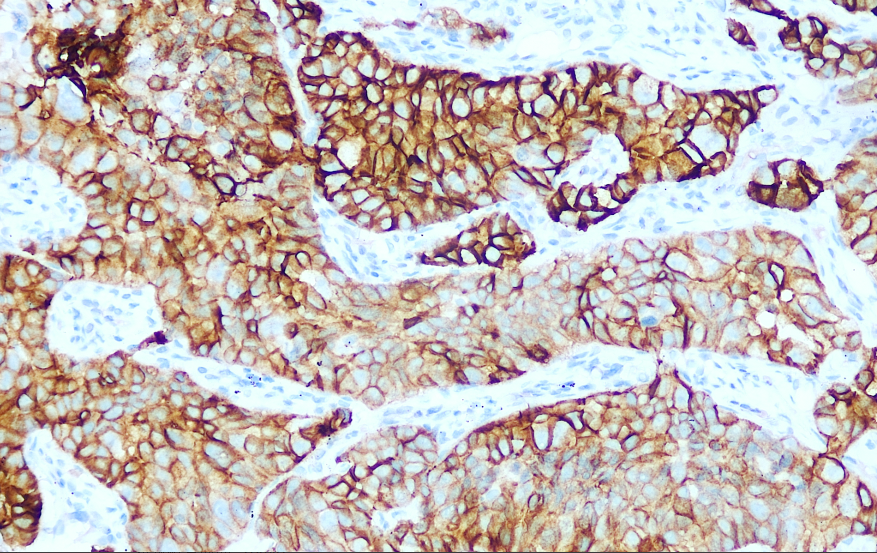

Positive control: Non-small cell lung cancer

Hepatocyte growth factor receptor (C-MET) is a tyrosine kinase receptor located on chromosome 7q21–31. It is expressed in epithelial cells of many organs, including lung cancer, liver cancer, breast cancer, and gastric cancer. Under normal conditions, the activation level of the C-MET signaling pathway is tightly regulated by the body after binding with hepatocyte growth factor (HGF). However, its abnormal activation can promote the occurrence and development of various types of tumors. Research indicates that C-MET serves as a critical therapeutic target for cancer treatment, with drugs such as C-MET monoclonal antibodies, HGF/C-MET antagonists, and C-MET small-molecule tyrosine kinase inhibitors providing more effective and diverse treatment options for clinical cancer therapy.

C-MET antibody reagents can specifically bind to C-MET molecular antigens. Immunohistochemistry kits containing C-MET antibody reagents are suitable for detecting c-MET protein overexpression or abnormal activation.